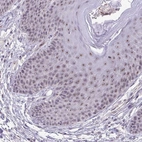

Immunohistochemical staining of human tonsil shows moderate positivity in nucleoli in non-germinal center cells.